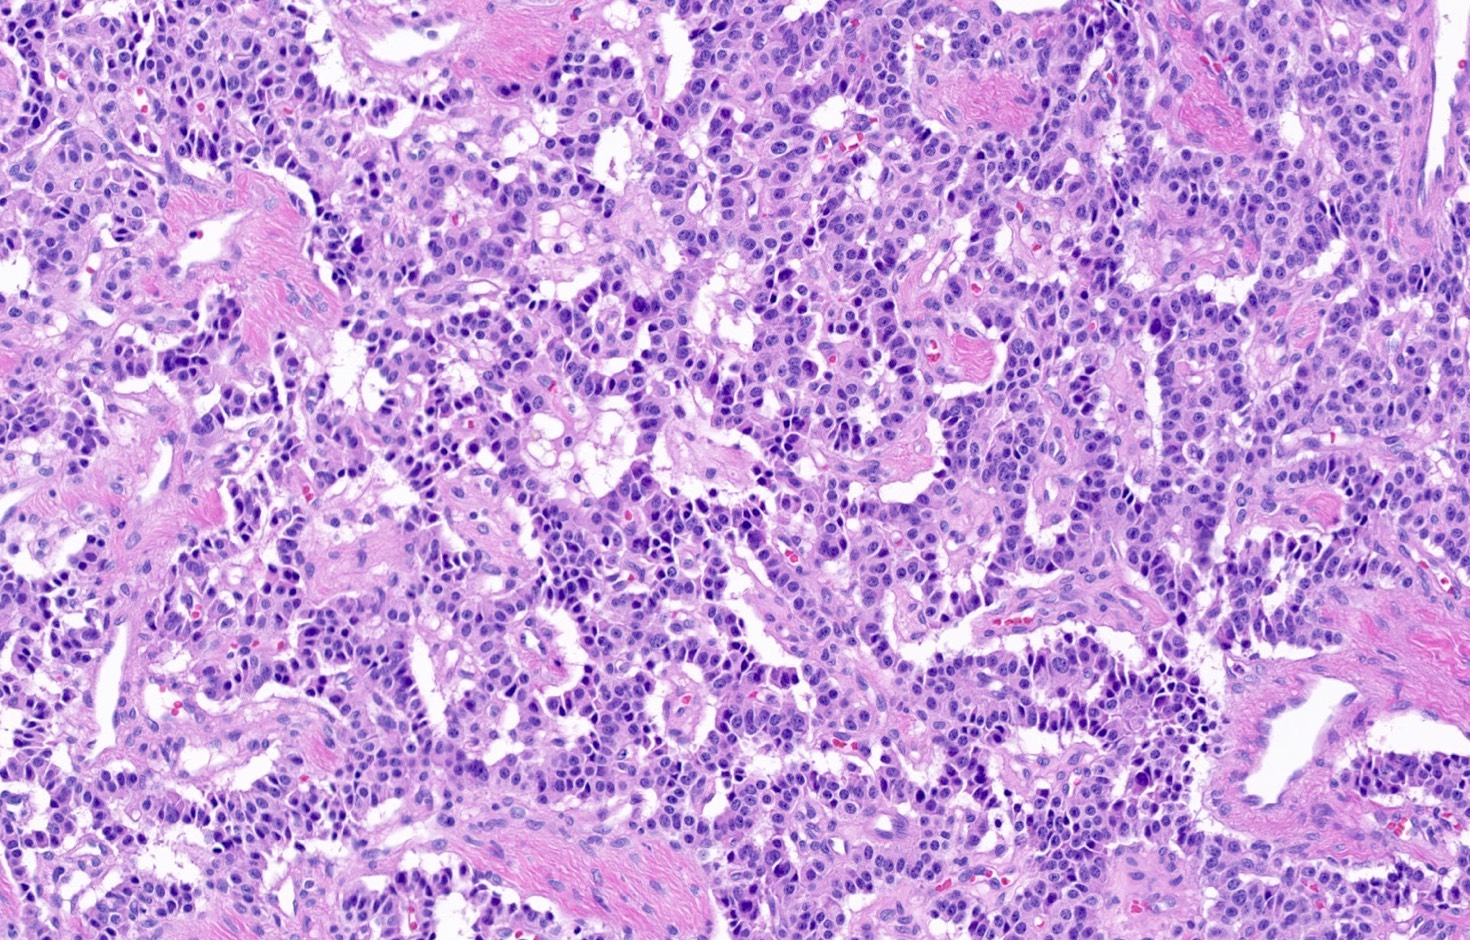

Microscopic (histologic) description

- Diagnostic criteria

- Neuroendocrine tumor with size ≥ 5 mm with < 2 mitoses/2 mm2 and absence of necrosis

- Neuroendocrine growth pattern (organoid, trabecular, rosette formation, nested) or pseudoglandular, follicular and papillary growth

- Tumor cells are uniform with a polygonal shape, round to oval nuclei with salt and pepper chromatin as well as inconspicuous nucleoli and moderate to abundant eosinophilic cytoplasm

- Spindle cells and clear cell features can be seen

- Stroma is fine and highly vascularized; hyalinization, cartilage or bone formation are possible

- Reference: Curr Oncol 2018;25:S86

Microscopic (histologic) images

Contributed by Philippe Joubert, M.D., Ph.D., Jijgee Munkhdelger, M.D., Ph.D. and Andrey Bychkov, M.D., Ph.D.

A 55 year old woman had a lower left lobectomy showing a well circumscribed flesh colored tumor. Histologic details are shown in the image above. Regarding this entity, which of the following statements is true?

A. CDX2 is usually negative in the lung and is useful to differentiate from a metastasis of an intestinal origin. The image shows a tumor with a trabecular pattern and pseudorosettes. The stroma is highly vascularized. Tumor cells are monotonous with scant to moderate eosinophilic cytoplasm. Nuclei are round to oval with salt and pepper chromatin and inconspicuous nucleoli. No mitoses are seen. These features are consistent with a typical carcinoid lung tumor.